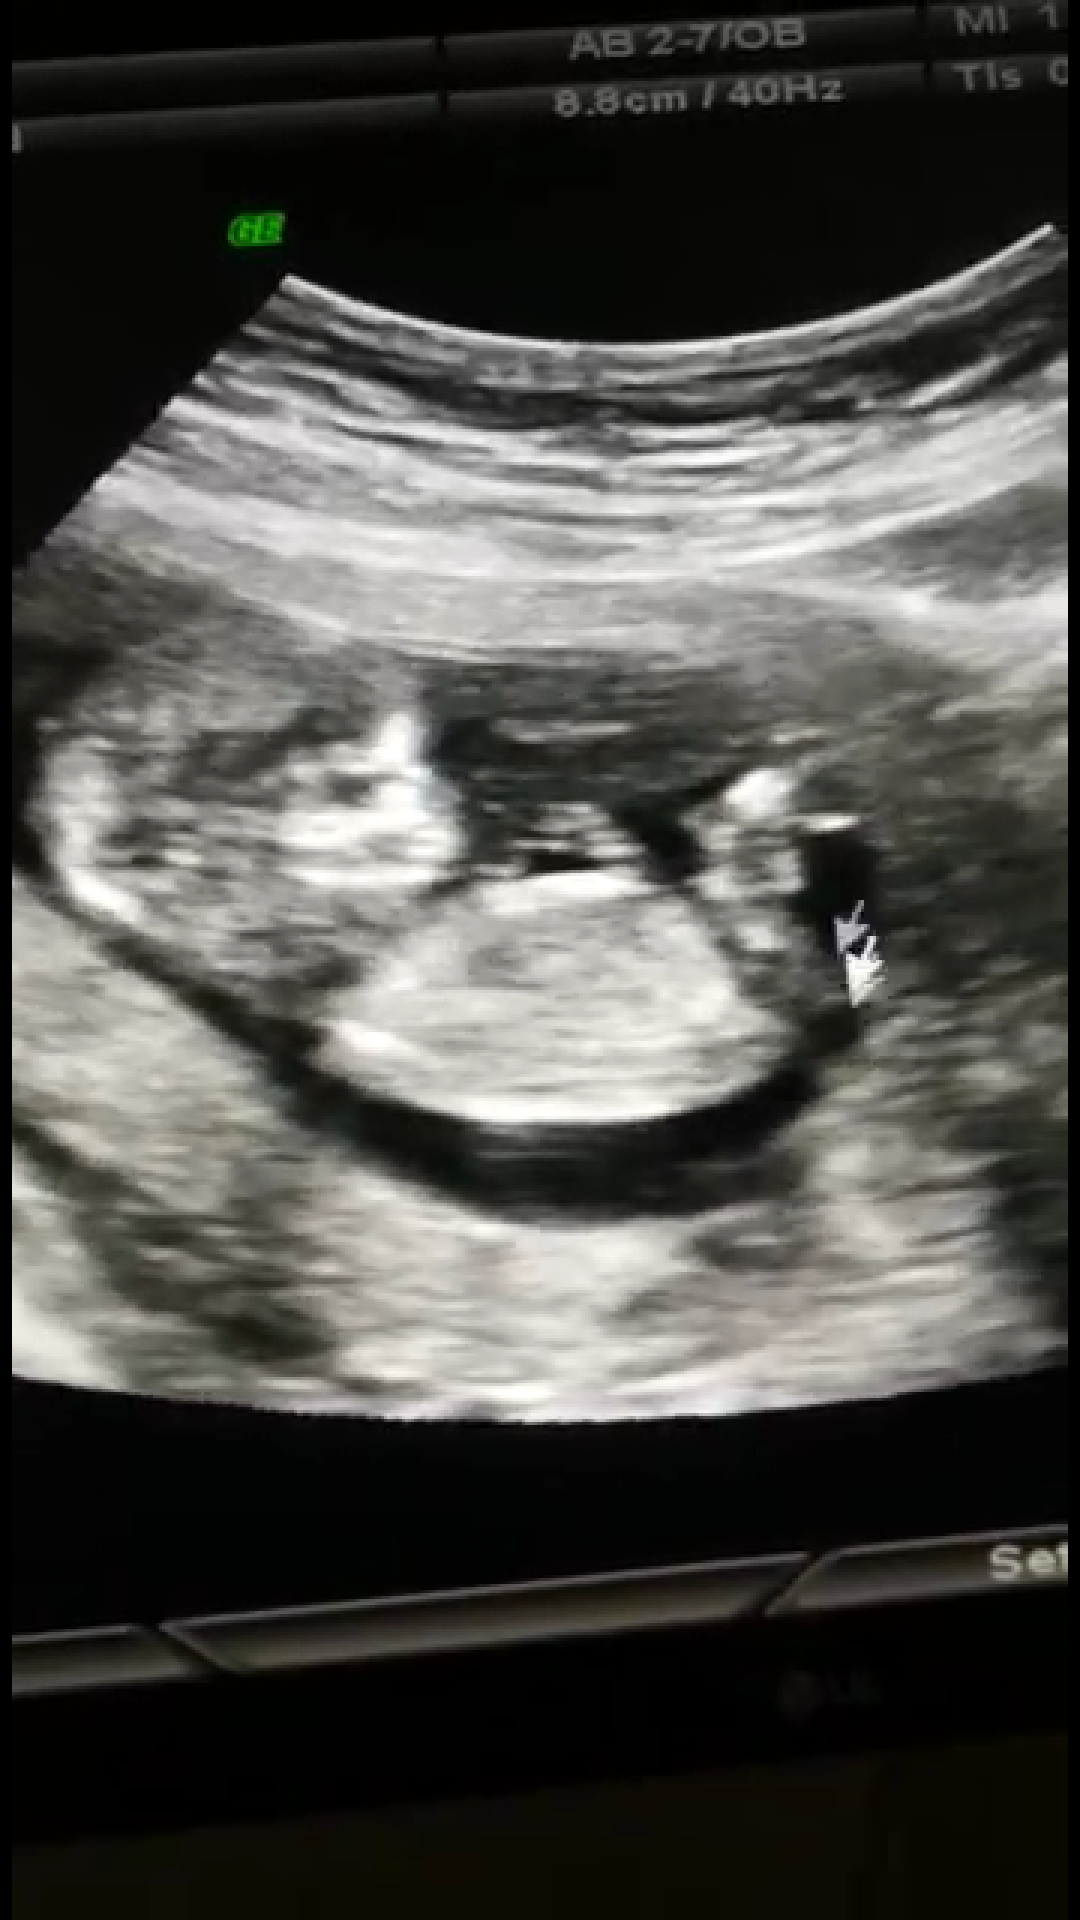

Canim benimkinde bakar mısın 12+1

Ekli dosyalar

• IMG_20211118_153757.jpg

IMG_20211118_153757.jpg

2 MB · Görüntüleme: 255

• IMG_20211118_153746.jpg

IMG_20211118_153746.jpg

1,6 MB · Görüntüleme: 261

• Screenshot_20211118-152347.jpg

Screenshot_20211118-152347.jpg

627 KB · Görüntüleme: 253